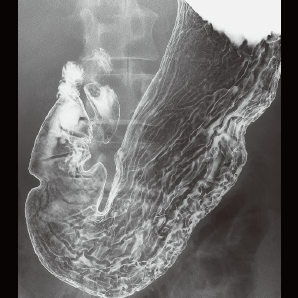

l 数字化造影

可以进行对比研究,例如食管造影、静脉肾盂造影和输卵管造影